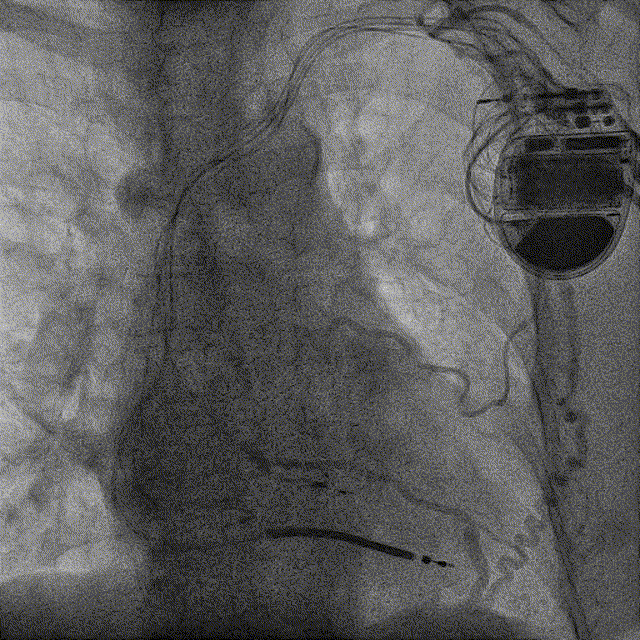

手术中,潘小宏主任团队首先使用锁定导丝锁定除颤导线,随后使用 11F 机械扩张鞘沿除颤导线分离粘连组织,顺利拔除位于右心室除颤电极导线。

机械扩张鞘拔除ICD导线